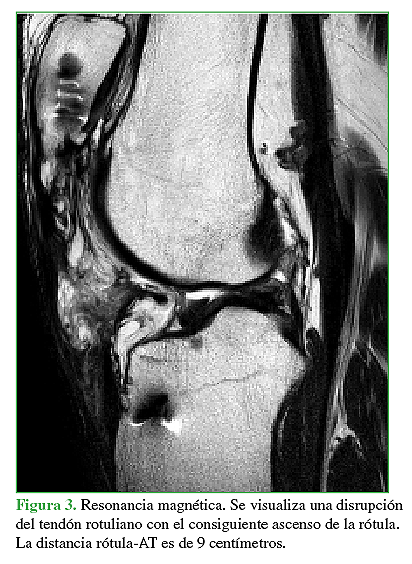

El objetivo de este trabajo es la presentación de un caso donde se realizó la reconstrucción quirúrgica del aparato extensor mediante la utilización de aloinjerto luego de haber presentado tres cirugías fallidas para la reparación del tendón rotuliano tras sufrir una lesión traumática del mismo. Se describe tanto la técnica quirúrgica como también el protocolo de rehabilitación.